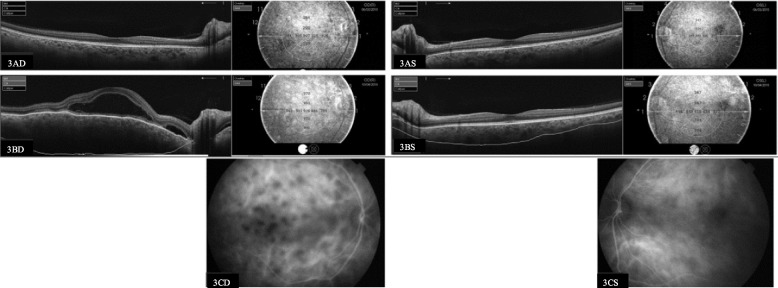

Purpose: The course of Vogt-Koyanagi-Harada (VKH) disease is typically assessed qualitatively using indocyanine green angiography (ICGA) and enhanced-depth imaging optical coherence tomography (EDI-OCT). However, a quantitative approach could improve accuracy and objectivity. The aim of this study was to assess the clinical value of the automated measurement capabilities of swept-source optical coherence tomography (SS-OCT) to measure choroidal thickness (quantitative approach) in chronic VKH.

Methods: Prospective, longitudinal case-control study at a tertiary university hospital involving 23 chronic VKH patients (9 convalescent and 14 quiescent) and 17 age-matched controls. Choroidal thickness was automatically measured with SS-OCT.

Results: Choroidal thinning and improved vision were associated with treatment while increasing thickness and worsening vision were associated with posterior relapse. Overall, 41.6% of asymptomatic (no change in visual acuity) recurrences in the convalescent group and 25% of recurrences in the quiescent group were detected by SS-OCT. All recurrences diagnosed by SS-OCT showed signs of inflammation on ICGA.

Conclusions: Automatic measurement of choroidal thickness with SS-OCT is a rapid, non-invasive method of detecting posterior segment recurrences and treatment response in VKH patients, and could reduce the need for angiography to monitor this disease.